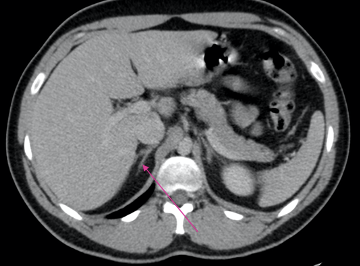

What is indicated by the arrow?

Lateral limb of adrenal gland

Medial limb of adrenal gland